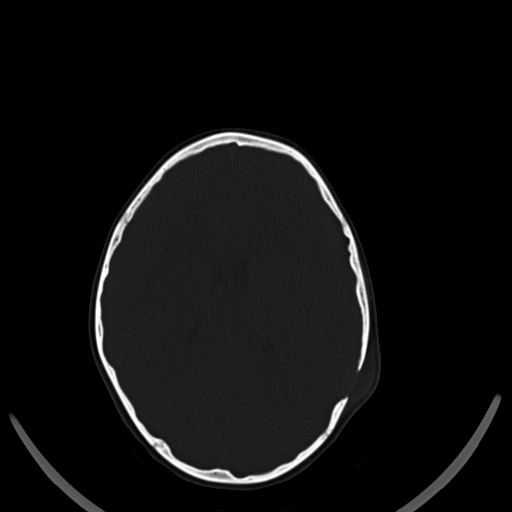

A. � un bambino di 7 anni che giunge in PS per la comparsa di una tumefazione molle in sede parietale sinistra associata a intenso dolore locale ed irritabilit� da alcuni giorni. In anamnesi trauma cranico 15 giorni prima senza sintomi associati. A. � in buone condizioni generali e l'obiettivit�, compresa quella neurologica, � nella norma. Anche gli esami ematici risultano nella norma. Vista la clinica e la storia di trauma cranico, eseguiamo TC cranio che mostra: �in sede extra-assiale parietale sinistra, apprezzabile sottile aspetto tenuemente iperdenso di larghezza 17 mm e spessore 5 mm; in corrispondenza, area tondeggiante di osteolisi di 10 x 10 mm a margini netti, con tumefazione delle parti molli extracraniche�. Per approfondimento diagnostico, eseguiamo RMN cerebrale che evidenzia: �formazione a densit� intermedia di diametro 4 x 2,5 cm in sede parietale sinistra che si localizza su entrambi i versanti del tavolato cranico, a ridosso dell'area di osteolisi.� In considerazione del reperto neuroradiologico, dopo consulenza Oncologica e Neurochirurgica, viene posto sospetto diagnostico di granuloma eosinofilo. Eseguite Rx torace ed eco addome che hanno escluso un possibile coinvolgimento viscerale. A. � stato quindi sottoposto ad intervento di curettage chirurgico che ha dato conferma istologica della diagnosi.